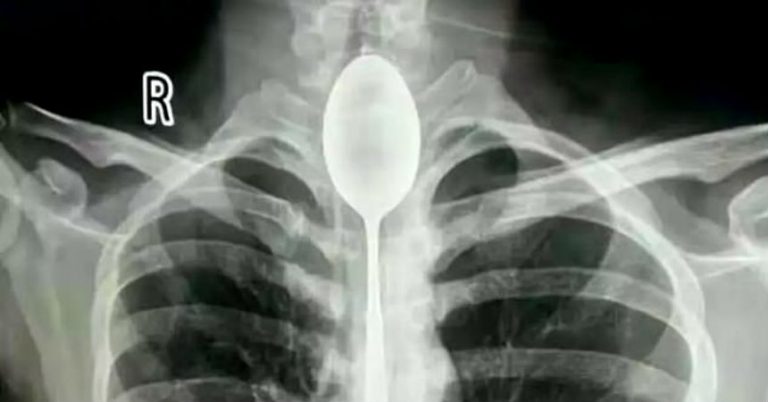

Hombre vivió durante un año con una cuchara de 20 centímetros atorada en su esófago

Es lo que ocurrió con un hombre de 26 años que llegó al Hospital General de Xinjiang Meikuang, en China, con una cuchara de 20 centímetros atorada en el esófago. Lo más curioso es que el objeto lo tenía alojado hace un año en su interior, según señala Daily Mail.

«Quedé impactado. Nunca he tenido algo así», dijo Yu Xiwu uno de los médicos que trató al paciente, el cual ya tenía complicaciones en su cuerpo lo que le había provocado una infección en esófago.

Según reconoció el paciente, de apellido Zhang, todo se debió a una apuesta que hizo con unos amigos, donde aseguró que era capaz de tragarse una cuchara. El hombre cumplió su palabra y lo hizo. El problema es que luego no pudo sacársela y anduvo un año con el objeto dentro de su cuerpo.

El hombre señaló que no había acudido antes al hospital porque en ningún momento le había molestado para hablar o comer. Sin embargo, un día recibió un golpe en el pecho lo que le provocó complicaciones derivadas a la cuchara que tenía en esófago.

Afortunadamente los médicos pudieron extraer la cuchara y el hombre se recupera satisfactoriamente.

Fotos: Hospital General de Xinjiang Meikuang